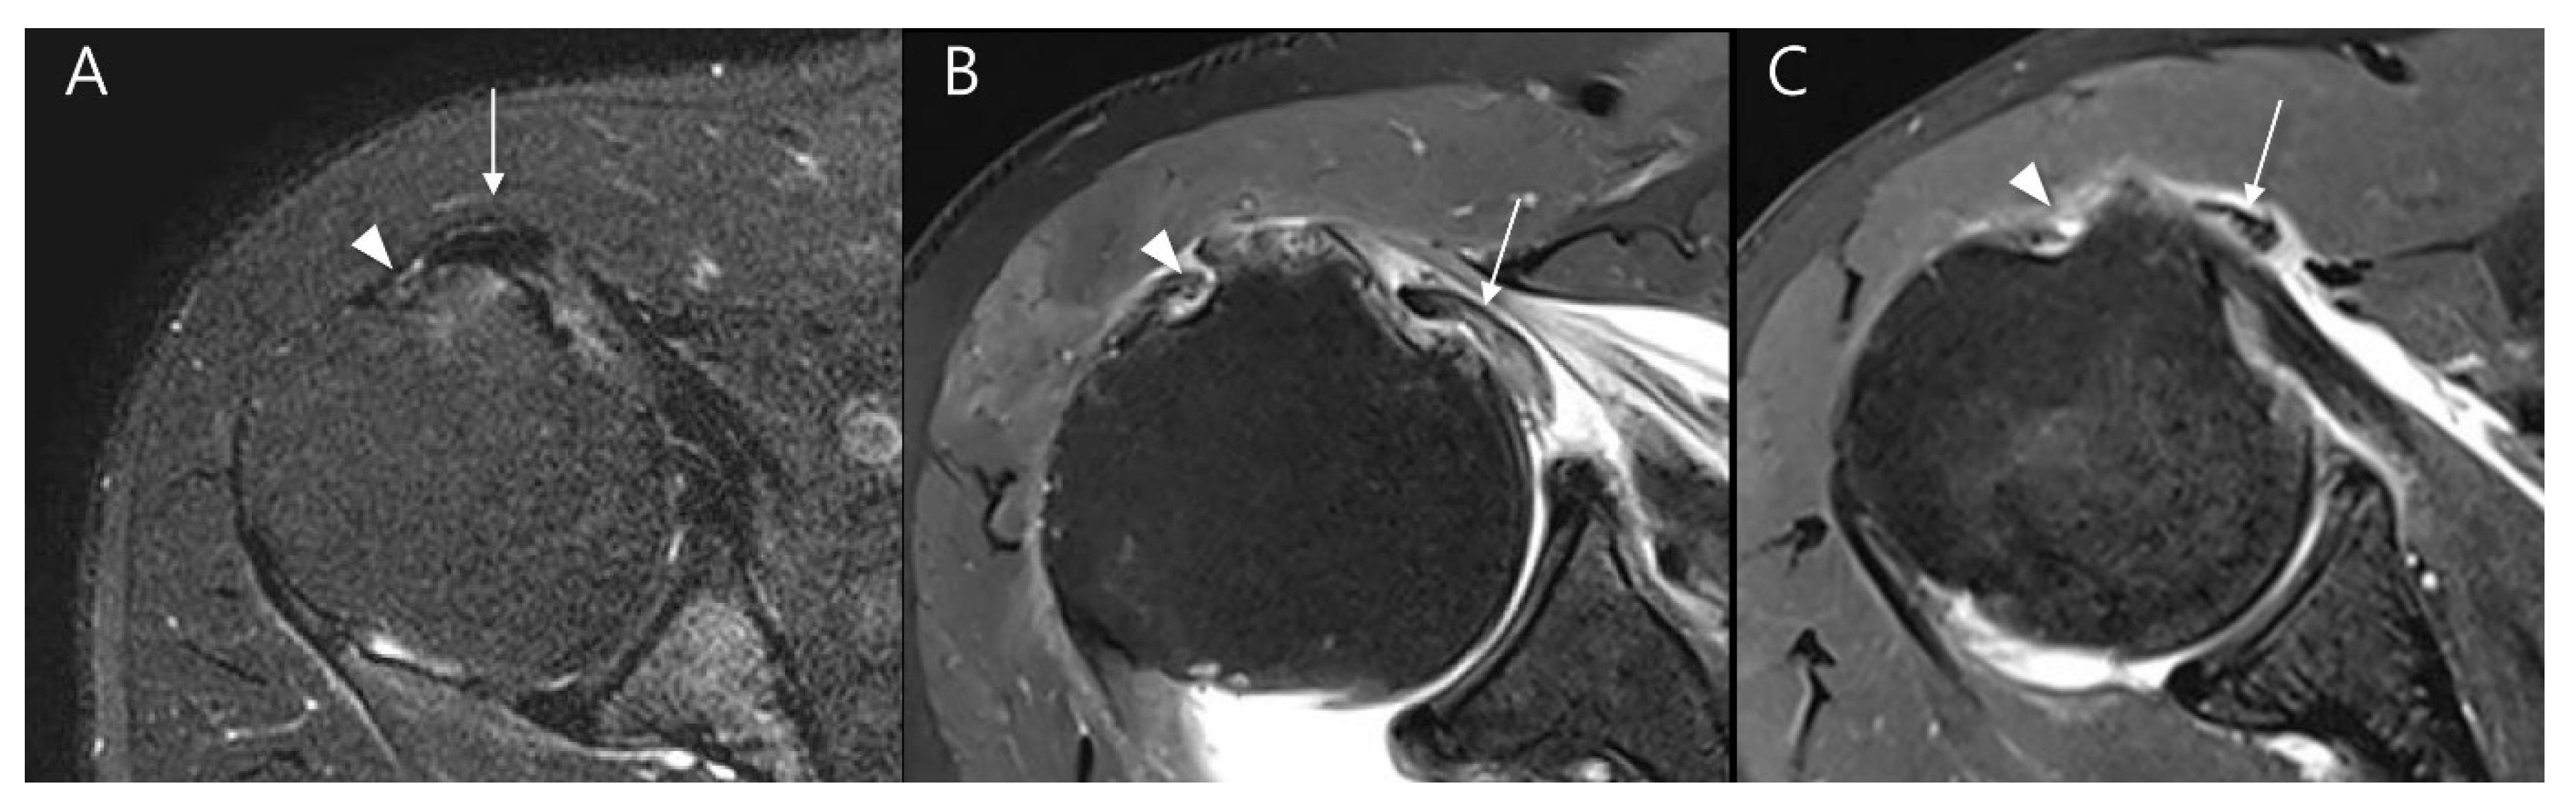

Figure 8.

Representative MR images of Yoo type IIA (A–C) and IIB (D–F) subscapularis tendon (SSC) tears: (A) T2-weighted oblique sagittal fat-suppressed image in a patient with a Yoo type IIA lesion demonstrates a partial thickness tear of the SSC with ≤50% detachment from the first facet (arrow). (B) T2-weighted oblique axial fat-suppressed image shows an intact long head of the biceps tendon (LHBT, arrowhead) in the bicipital groove. (C) The T2-weighted oblique sagittal image shows no muscle atrophy. (D) T2-weighted oblique sagittal fat-suppressed image in a patient with a Yoo type IIB lesion demonstrates a partial thickness tear of the SSC > 50% detachment from the first facet (arrow). (E) T2-weighted oblique axial fat-suppressed image shows subluxation of LHBT (arrowhead) from the bicipital groove (curved arrow). (F) T2-weighted oblique sagittal image shows moderate muscle atrophy, especially in the upper half. BT, biceps tendon.